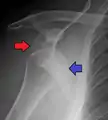

A Hill–Sachs lesion is an impaction of the head of the humerus left by the glenoid rim during dislocation.[6] Hill-Sachs deformities occur in 35–40% of anterior dislocations. They can be seen on a front-facing X-ray when the arm is in internal rotation.[9] Bankart lesions are disruptions of the glenoid labrum with or without an avulsion of bone fragment.

Anterior dislocation of the right shoulder. AP X ray

Anterior dislocation of the right shoulder. Y view X ray.